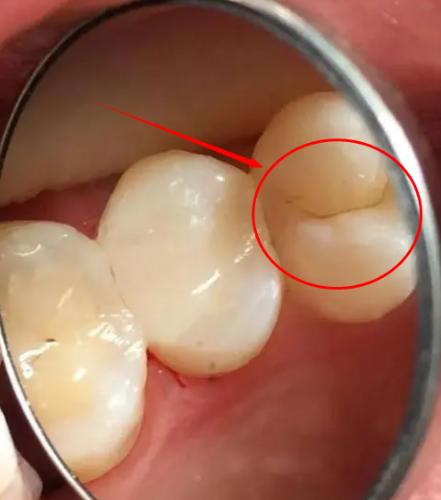

“悲剧还是发生了”!浙江杭州一女子吃大闸蟹时,用牙齿将大闸蟹腿咬开,正当要品尝美味,却突然感到牙齿一阵剧痛,随后竟然连喝水都疼,女子受不了了就去医院检查,结果发现牙被蟹腿崩“裂”了,需要进行根管治疗。 秋风送爽之时,正是品尝大闸蟹的黄金时节,当那份独有的鲜美在舌尖绽放,谁能想到一场口腔里的“灾难”正在悄然酝酿。 浙江杭州的李女士,就因为贪图方便用牙齿去啃蟹腿,结果付出了不小的代价,这可不是什么稀奇事,给了我们每个人提醒。 我们那口引以为傲的牙,有时候比想象中要脆弱得多,牙齿的作用更多是为了咀嚼,而不是当“钳子”使,平时我们吃米饭,咬合力是完全够用的。 可一旦对上大闸蟹的硬壳、香脆的核桃,甚至是啤酒瓶盖时,就已经远超平时吃饭时的咬合力了,这种超负荷的冲击,最喜欢找牙齿的“软肋”下手。 比如你牙齿上本身就有一点小蛀洞,或者有一块补了很久的填充材料,这些地方就是天然的薄弱点。 对于上了年纪的中老年人来说,牙齿本身就会变得更脆,风险就更大了,可能平时啃个硬骨头就中招了,当那声不祥的“咔”在嘴里响起,牙齿的警报就拉响了。 李女士形容那种痛,就像突然被“电击”中一样,尖锐得能钻进骨头里,很快半边脸都跟着疼起来,更要命的是,这种时候连喝口温水都成了一种“酷刑”,会引发剧烈的疼痛。 这可不是普通的牙疼,而是牙齿内部结构被撕裂的“信号”,医生用小镜子和探针一检查,就能发现那道细微的裂纹。 它可能已经从牙齿表面,一路向下延伸,触碰到了布满神经的牙髓,牙齿用最痛苦的方式,表明自己所处的“困境”,“它”受了重伤! 处理这种隐形裂痕,就像一场和时间的“赛跑”,越拖后果越严重,如果裂纹还很浅,只伤到最外层,用树脂补一下就行。 但要是裂纹深了一些,影响到了牙本质,那就得先垫个底再修补,万一裂纹深到像李女士那样,直通牙神经,那就得做根管治疗了。 这套流程可不简单,要把坏死的神经清理干净,再用特殊材料把里面填满,来来回回得跑好几趟医院,而且治疗完还不算结束。 失去神经的牙齿会变脆,必须再给它戴个牙冠保护起来,否则下次吃东西可能整个牙就劈了,要是你心存侥幸,觉得忍忍就过去了,那小裂纹只会越裂越深。 还会引发牙髓炎、牙根发炎,牙龈上鼓起脓包,到了那个地步,这颗牙大概率是保不住了,只能拔掉再花大价钱去种一颗新牙,那才叫真的得不偿失。 牙齿是用来享受美食的,不是万能工具,真正的“吃货”不光懂吃,更懂怎么保护自己吃饭的“本钱”。 养成每半年或一年看牙医的习惯,让专业人士帮你提前发现问题,加固薄弱环节,这才是最高明的预防,毕竟善待你的牙齿,才能让世间美味长久相伴。